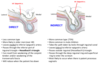

What is the difference between a direct and indirect hernia?

Inguinal Triangle Hesselbach’s Triangle?

- Medial border = Lateral margin of the rectus abdominis muscle/sheath

- Superolateral border = Inferior epigastric vessels

- Inferior border = Inguinal ligament (Poupart’s ligament)